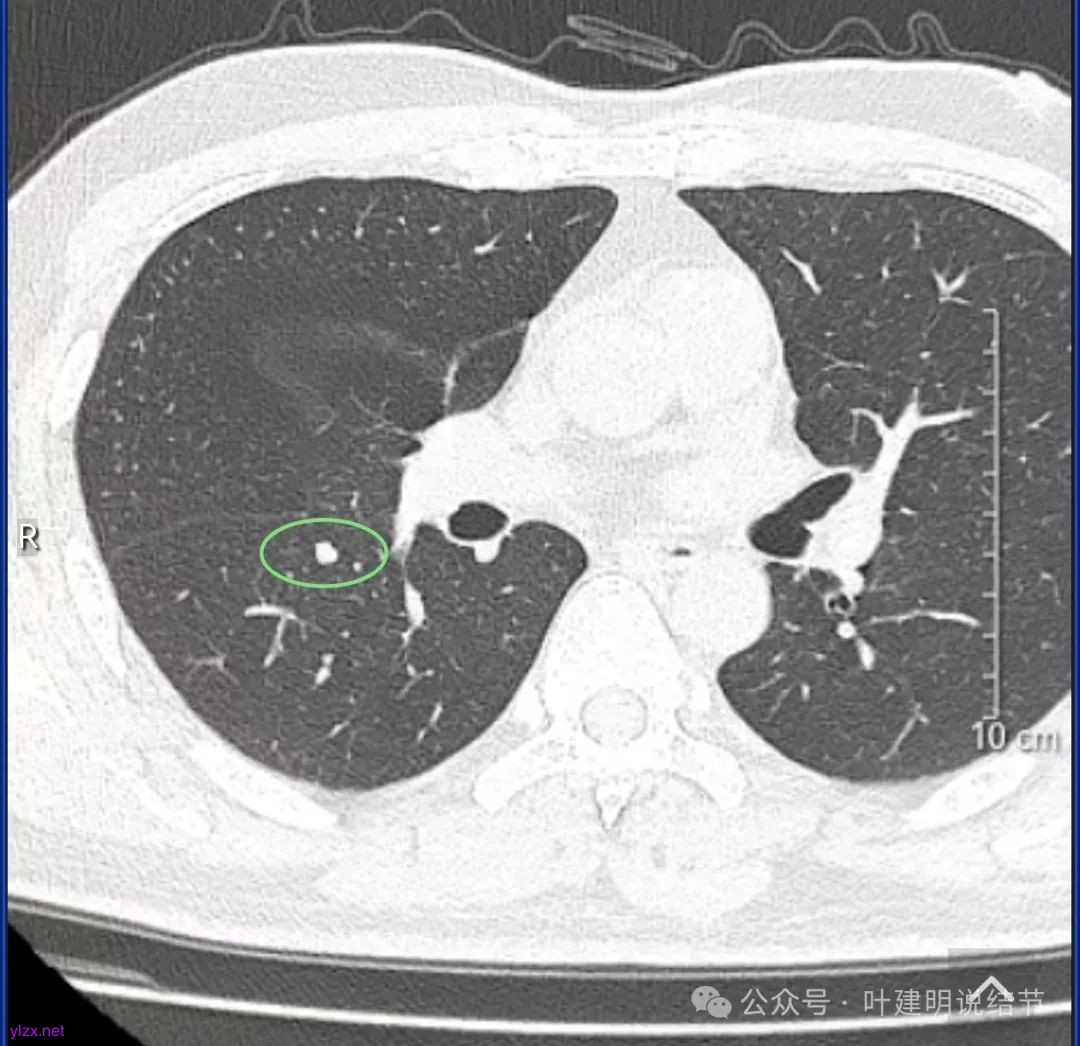

结友男性,41岁,具体病史记不得了,下面是请他重新发我的术前CT报告中截图的影像。

下叶背段有一实性结节,但没有找到其他磨玻璃结节。可以反馈的术后病理说下叶楔形切除了有个结节是肺泡上皮增生。大概不会是这处实性的,可能是很淡的,不容易找到的一处结节。算了,不管它。也不知道这处实性的有没有处理,还是不需要处理。